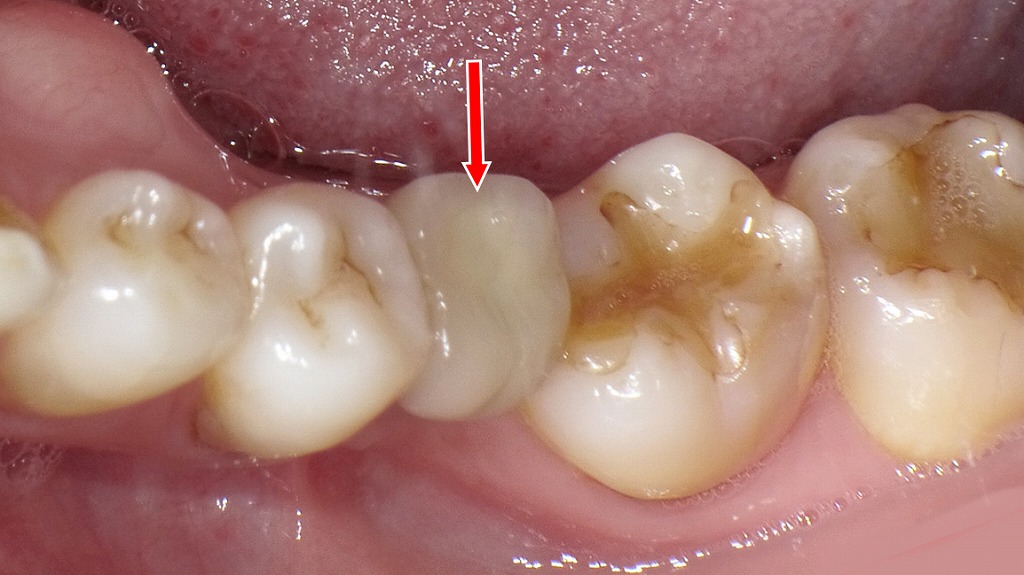

下顎6番相当部にインプラントを埋入し、適切な初期固定を得たうえでフルジルコニアクラウンを装着した症例です。レントゲンではインプラント体が周囲骨と良好に結合している様子が確認でき、口腔内写真では隣接歯と自然に調和した色調・形態で修復されていることがわかります。強度に優れたフルジルコニアにより、審美性と咀嚼機能の両面で長期的な安定が期待できる治療結果となっています。